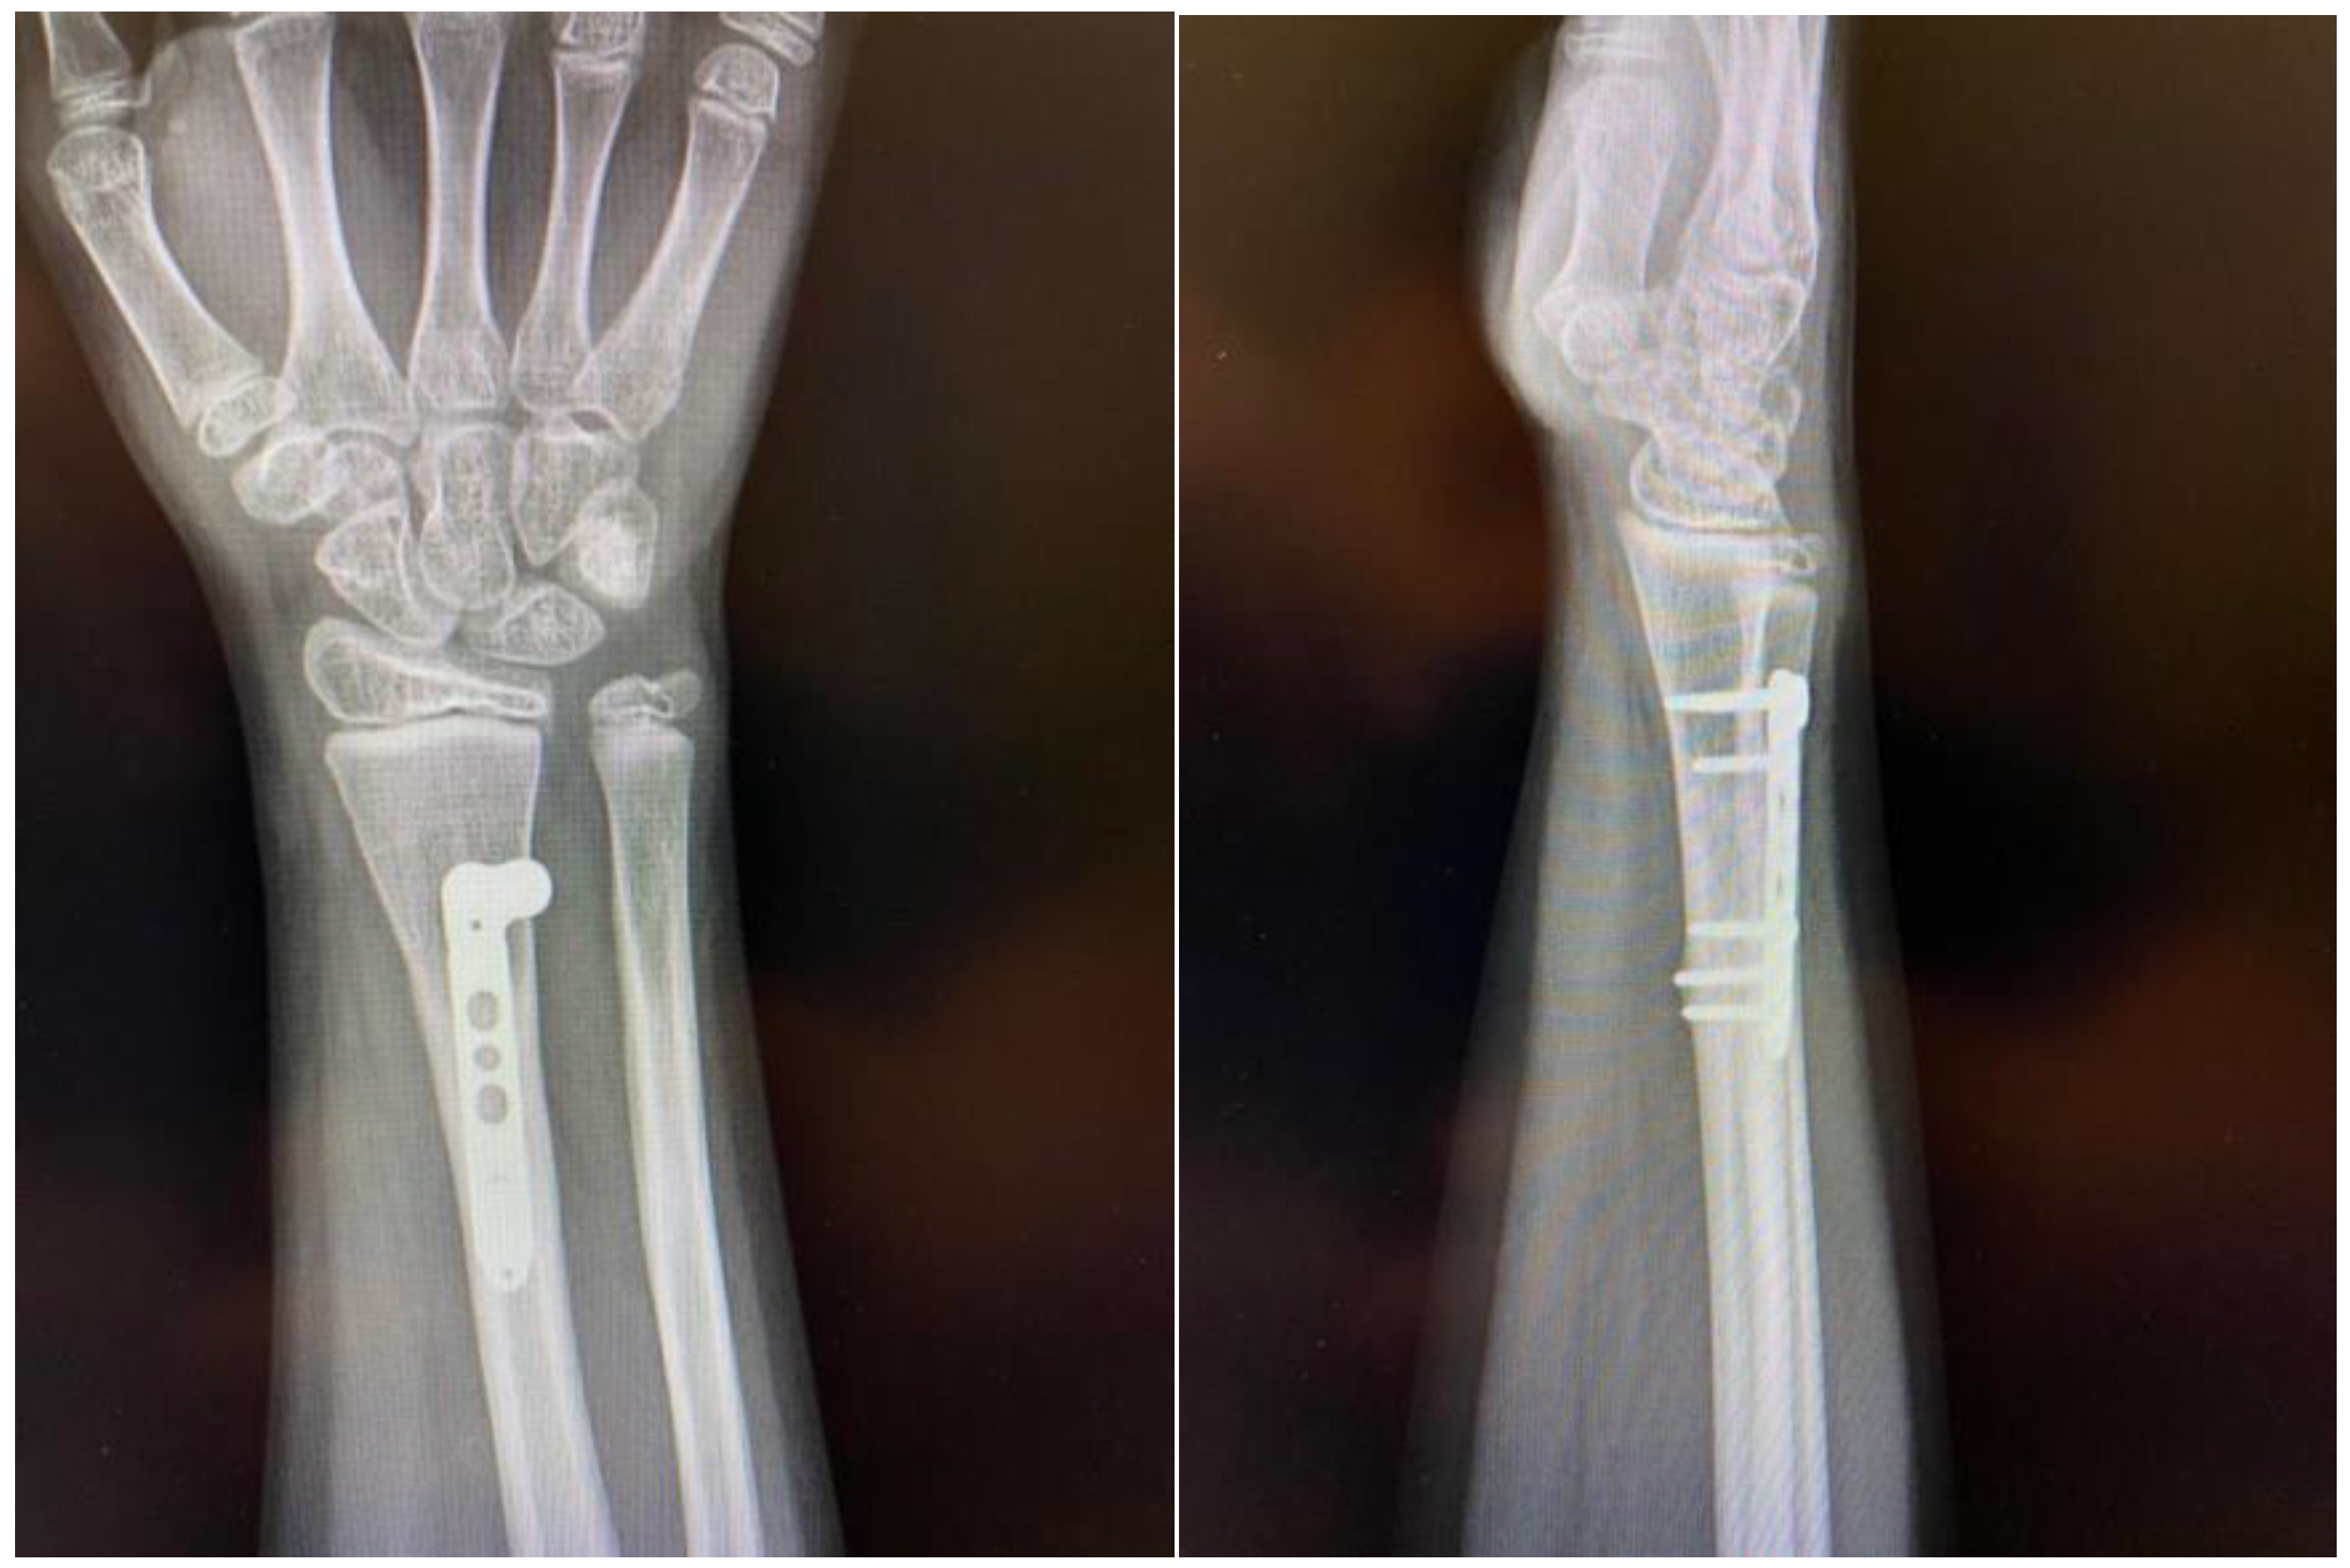

After identifying the tendon and the anatomical position, this was reduced and passed dorsally through the fracture site, retracted, and fixation was obtained under fluoroscopy using a locking plate, located proximally to the growth plate, with satisfactory reduction and absolute stability (Figure 5).

Post-operatively, no immobilization was required and mobility was allowed as tolerated without loading the hand for four weeks. At this time, the passive range of motion was normal while the active range of motion was slightly limited for flexion and extension of the wrist, and the patient underwent a 4-week rehabilitation program involving physical therapy exercises and mobility exercises. At 6 weeks post-operation our patient was pain-free with full range of motion. At week 8 the patient started strengthening exercises, and was allowed to return to high-demand sports after the 4-month follow-up clinical evaluation, which revealed full range of motion, passive and active, and no pain when loading the hand during active flexion and extension. At 12 months, we obtained a radiological control image (Figure 6) that confirmed healing and adequate callus formation as well as bone remodeling.

Figure 6. The 12-month follow-up plain radiographs demonstrating good healing and proper callus formation.